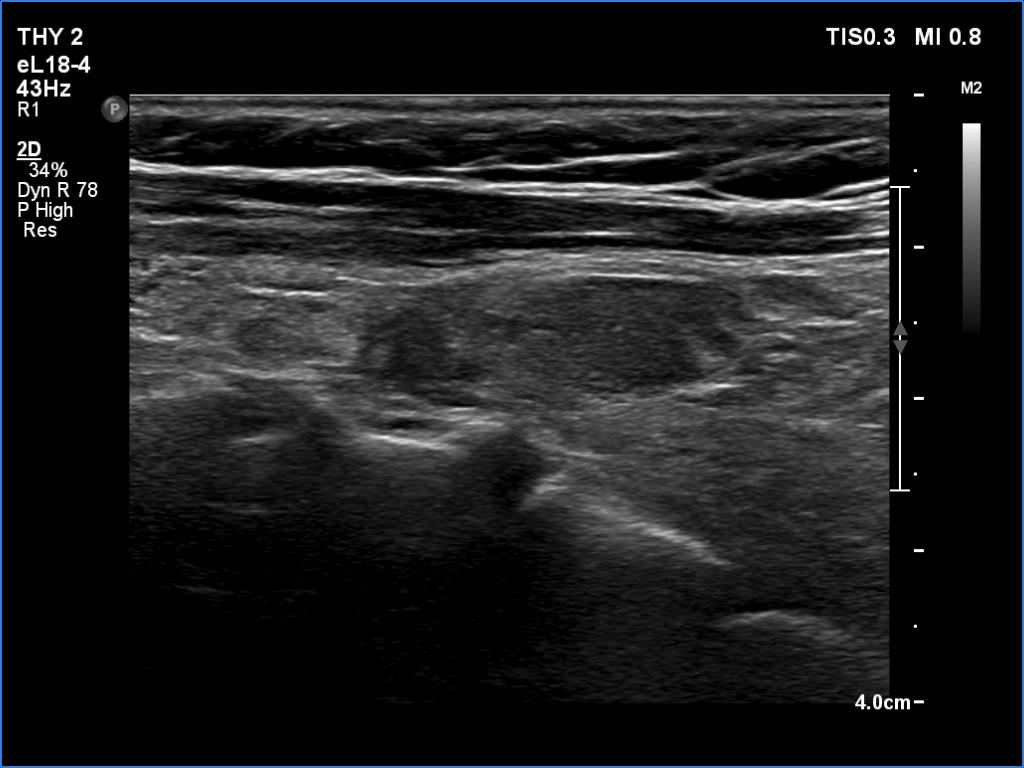

Ultrasonography. The thyroid was atrophic and hypoechoic. There was a hypoechoic mass under the lower pole of the left lobe.